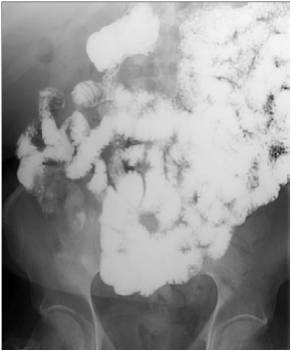

Image

Fig.20.: Follow-through examination

On the abdominal radiograph distension of the small bowel loops and air-fluid levels can be identified. It is important to describe forwarding of the contrast media by time or if mechanical obstruction is seen. Morphology of the intestinal loops could not be assessed with this method. This study is specifically conducted to examine the transit function only.

Fig.21.: Radiograph of selective enterocylsis